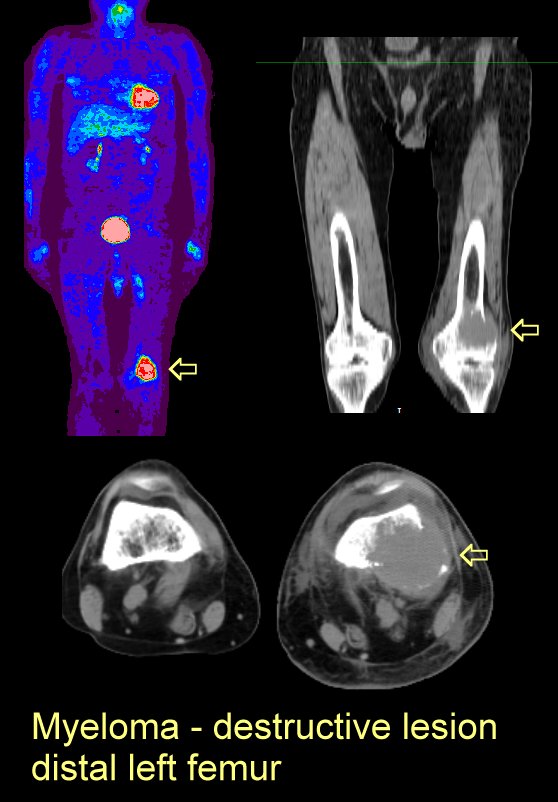

#6 Large destructive lesion in distal left femur on PET

and CT: here and

here